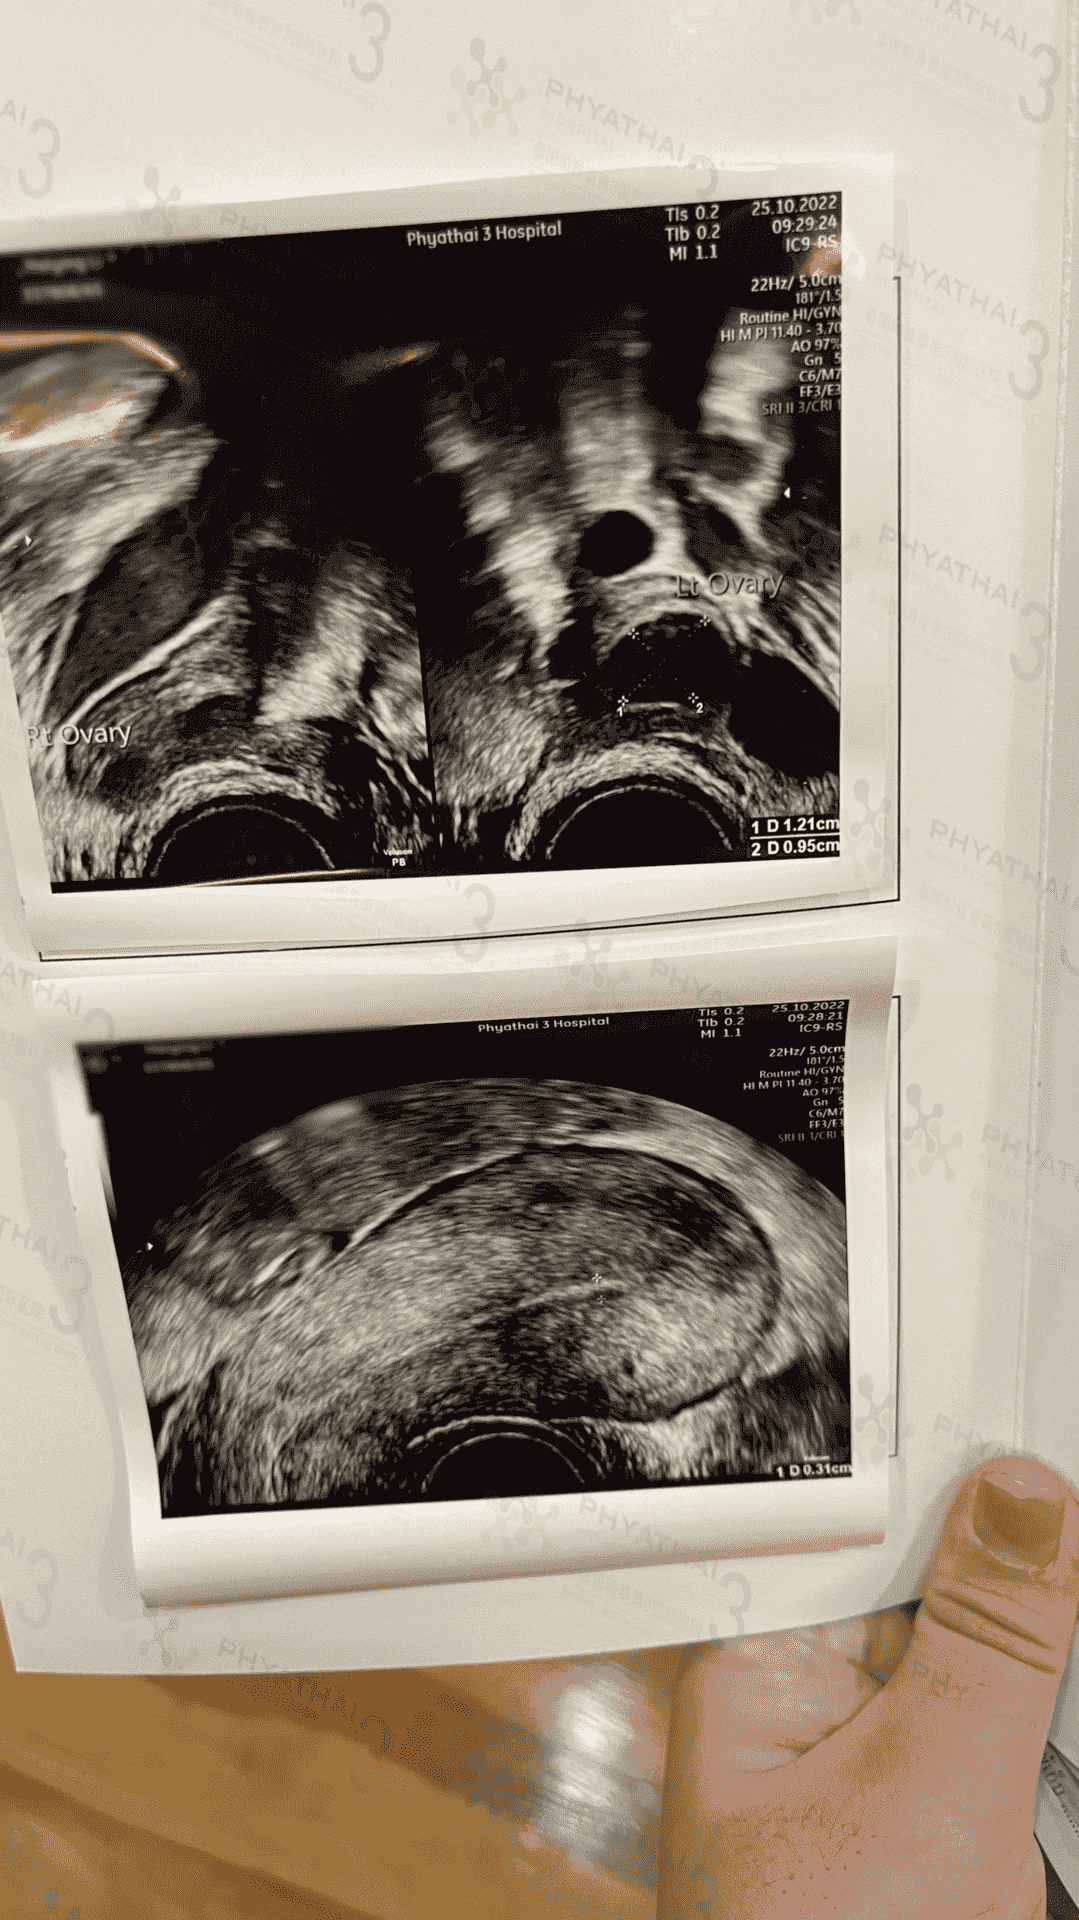

取卵手术后多长时间可以移植?

今天是我这位患者出院手术后的第二次月经的第2天,取卵手术后的第一次月经卵巢里面的卵泡还没有消,所以医生给女士安排了吃避孕药2周后就来月经,因为她取到了不少卵子,(看个人情况)今天检查医生说还有一点点没有消但是医生判断不影响,今天开始吃补佳乐,多6天贴内膜贴,希望下一次见诊内膜情况不错我们调理内膜要让卵巢恢复好情况下18-20天左右才可以胚胎移植手术哈,期待我们女士马上可以接宝宝回中国啦